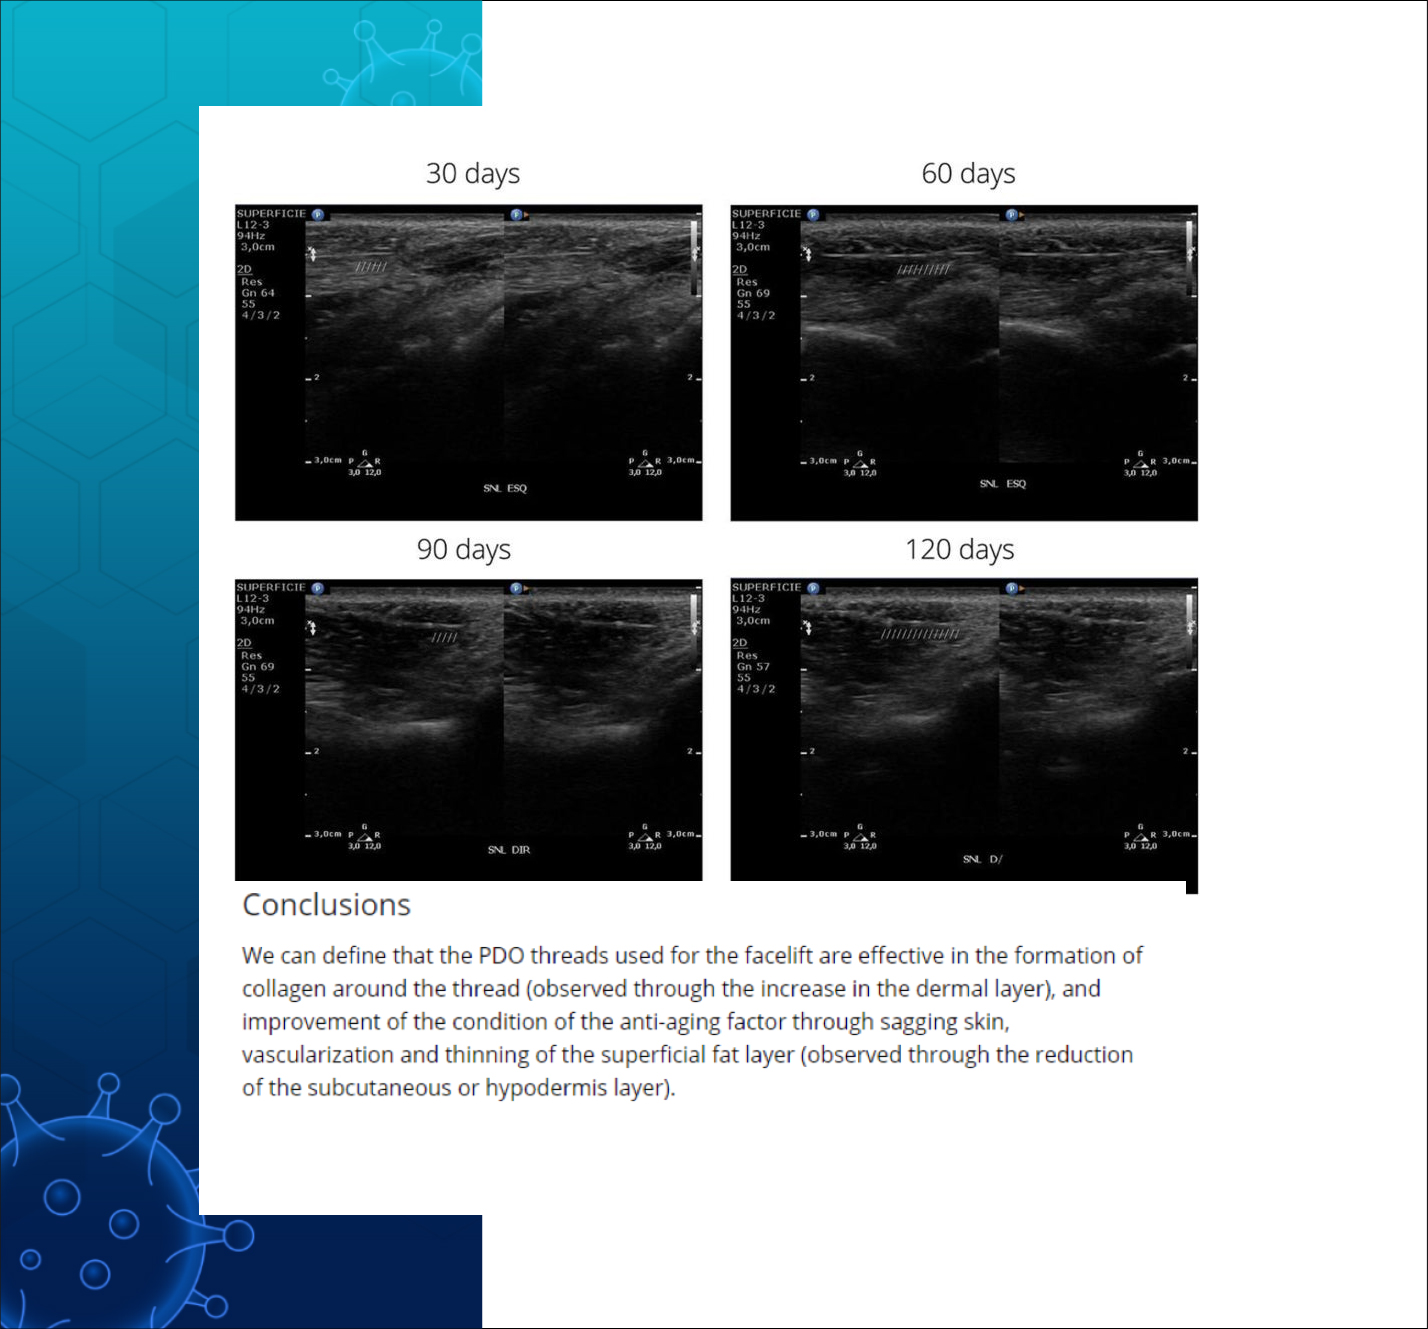

PDO실은 진피층의 두께는 증가시키고

(피부 탄력 증가)

혈관 형성을 촉진하며

콜라겐 형성을 촉진하고

피하지방층의 감소도 유발하는것으로

실험 대상 모두에게서

초음파 검사를 통해 관찰 되었다.

Effect of pdo facelift threads on facial skin tissues: An ultrasonographic

analysis - Lots - 2023 - Journal of Cosmetic Dermatology - Wiley Online

Library - https://onlinelibrary.wiley.com/doi/full/10.1111/jocd.15761